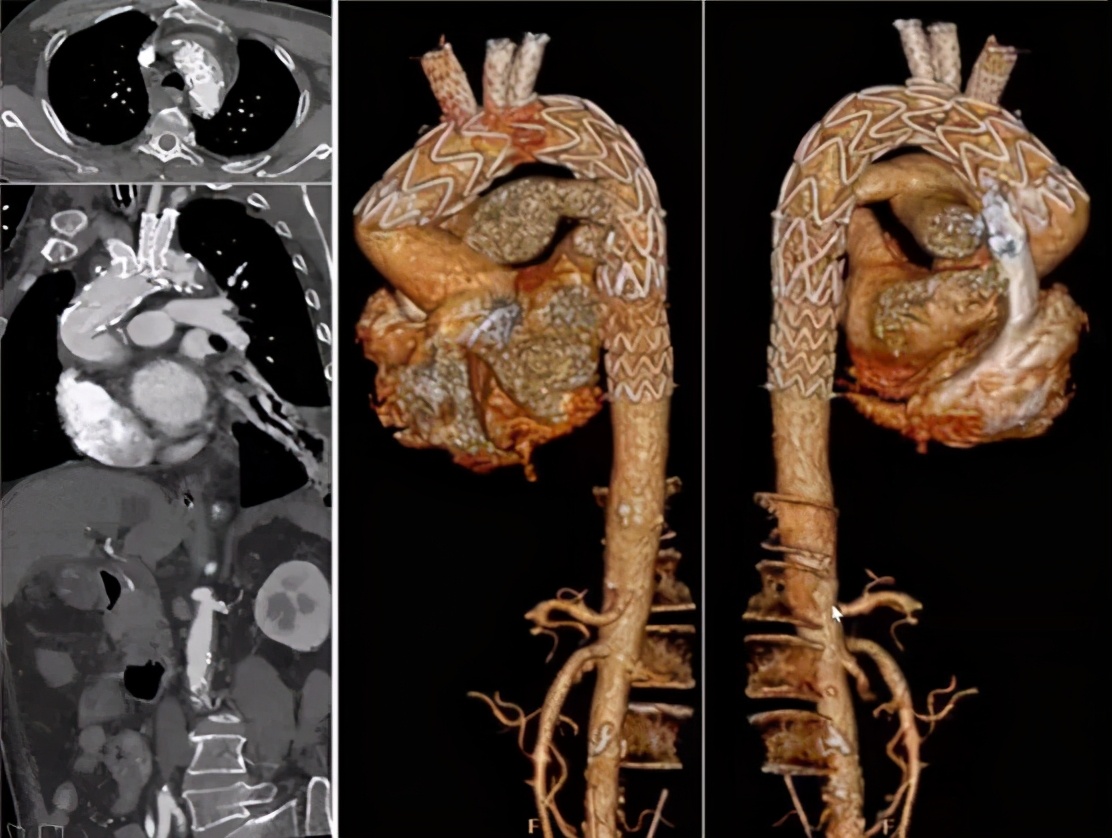

手术关注点:弓部动脉瘤原位开窗操作难度大,术中存在较大风险;而如果使用烟囱支架,则内漏风险大。所以,决定行预开窗+体外缝制内分支,增加重建弓上分支成功率,降低术中缺血风险、内漏风险。

手术方法:弓上三分支预开窗+内分支+主动脉腔内修复术。

手术步骤:弓上分支体外预开窗+内分支缝合;释放远端限制支架+近端主体支架;弓上分支支架植入。

病例4(男性,33岁)

主诉:急性胸背痛3小时。

既往史:高血压、糖尿病、马凡综合征。

手术史:3年前因“升主动脉瘤+AI(重度)”行Bentall手术。

手术方法:IA烟囱+LCCA三明治+LSA封堵+LCCA-LSA搭桥+主动脉腔内修复术。

手术步骤:左颈总动脉-左锁骨下动脉搭桥;胸降主动脉支架(Ⅱ)释放到位;无名动脉“烟囱”支架+左颈总动脉支架放置到位,不释放;近心端主动脉支架(Ⅰ)近段+无名动脉“烟囱”支架释放;升主动脉支架(Ⅰ)远端+左颈总动脉“三明治”支架释放;左锁骨下动脉起始部封堵。

术后:全腔内&平行支架技术是否适用于马凡综合征患者的主动脉弓部病变,目前远期效果仍存疑。术后5年随访显示弓部形态良好,远端胸降主动脉&腹主动脉存在扩张趋势。